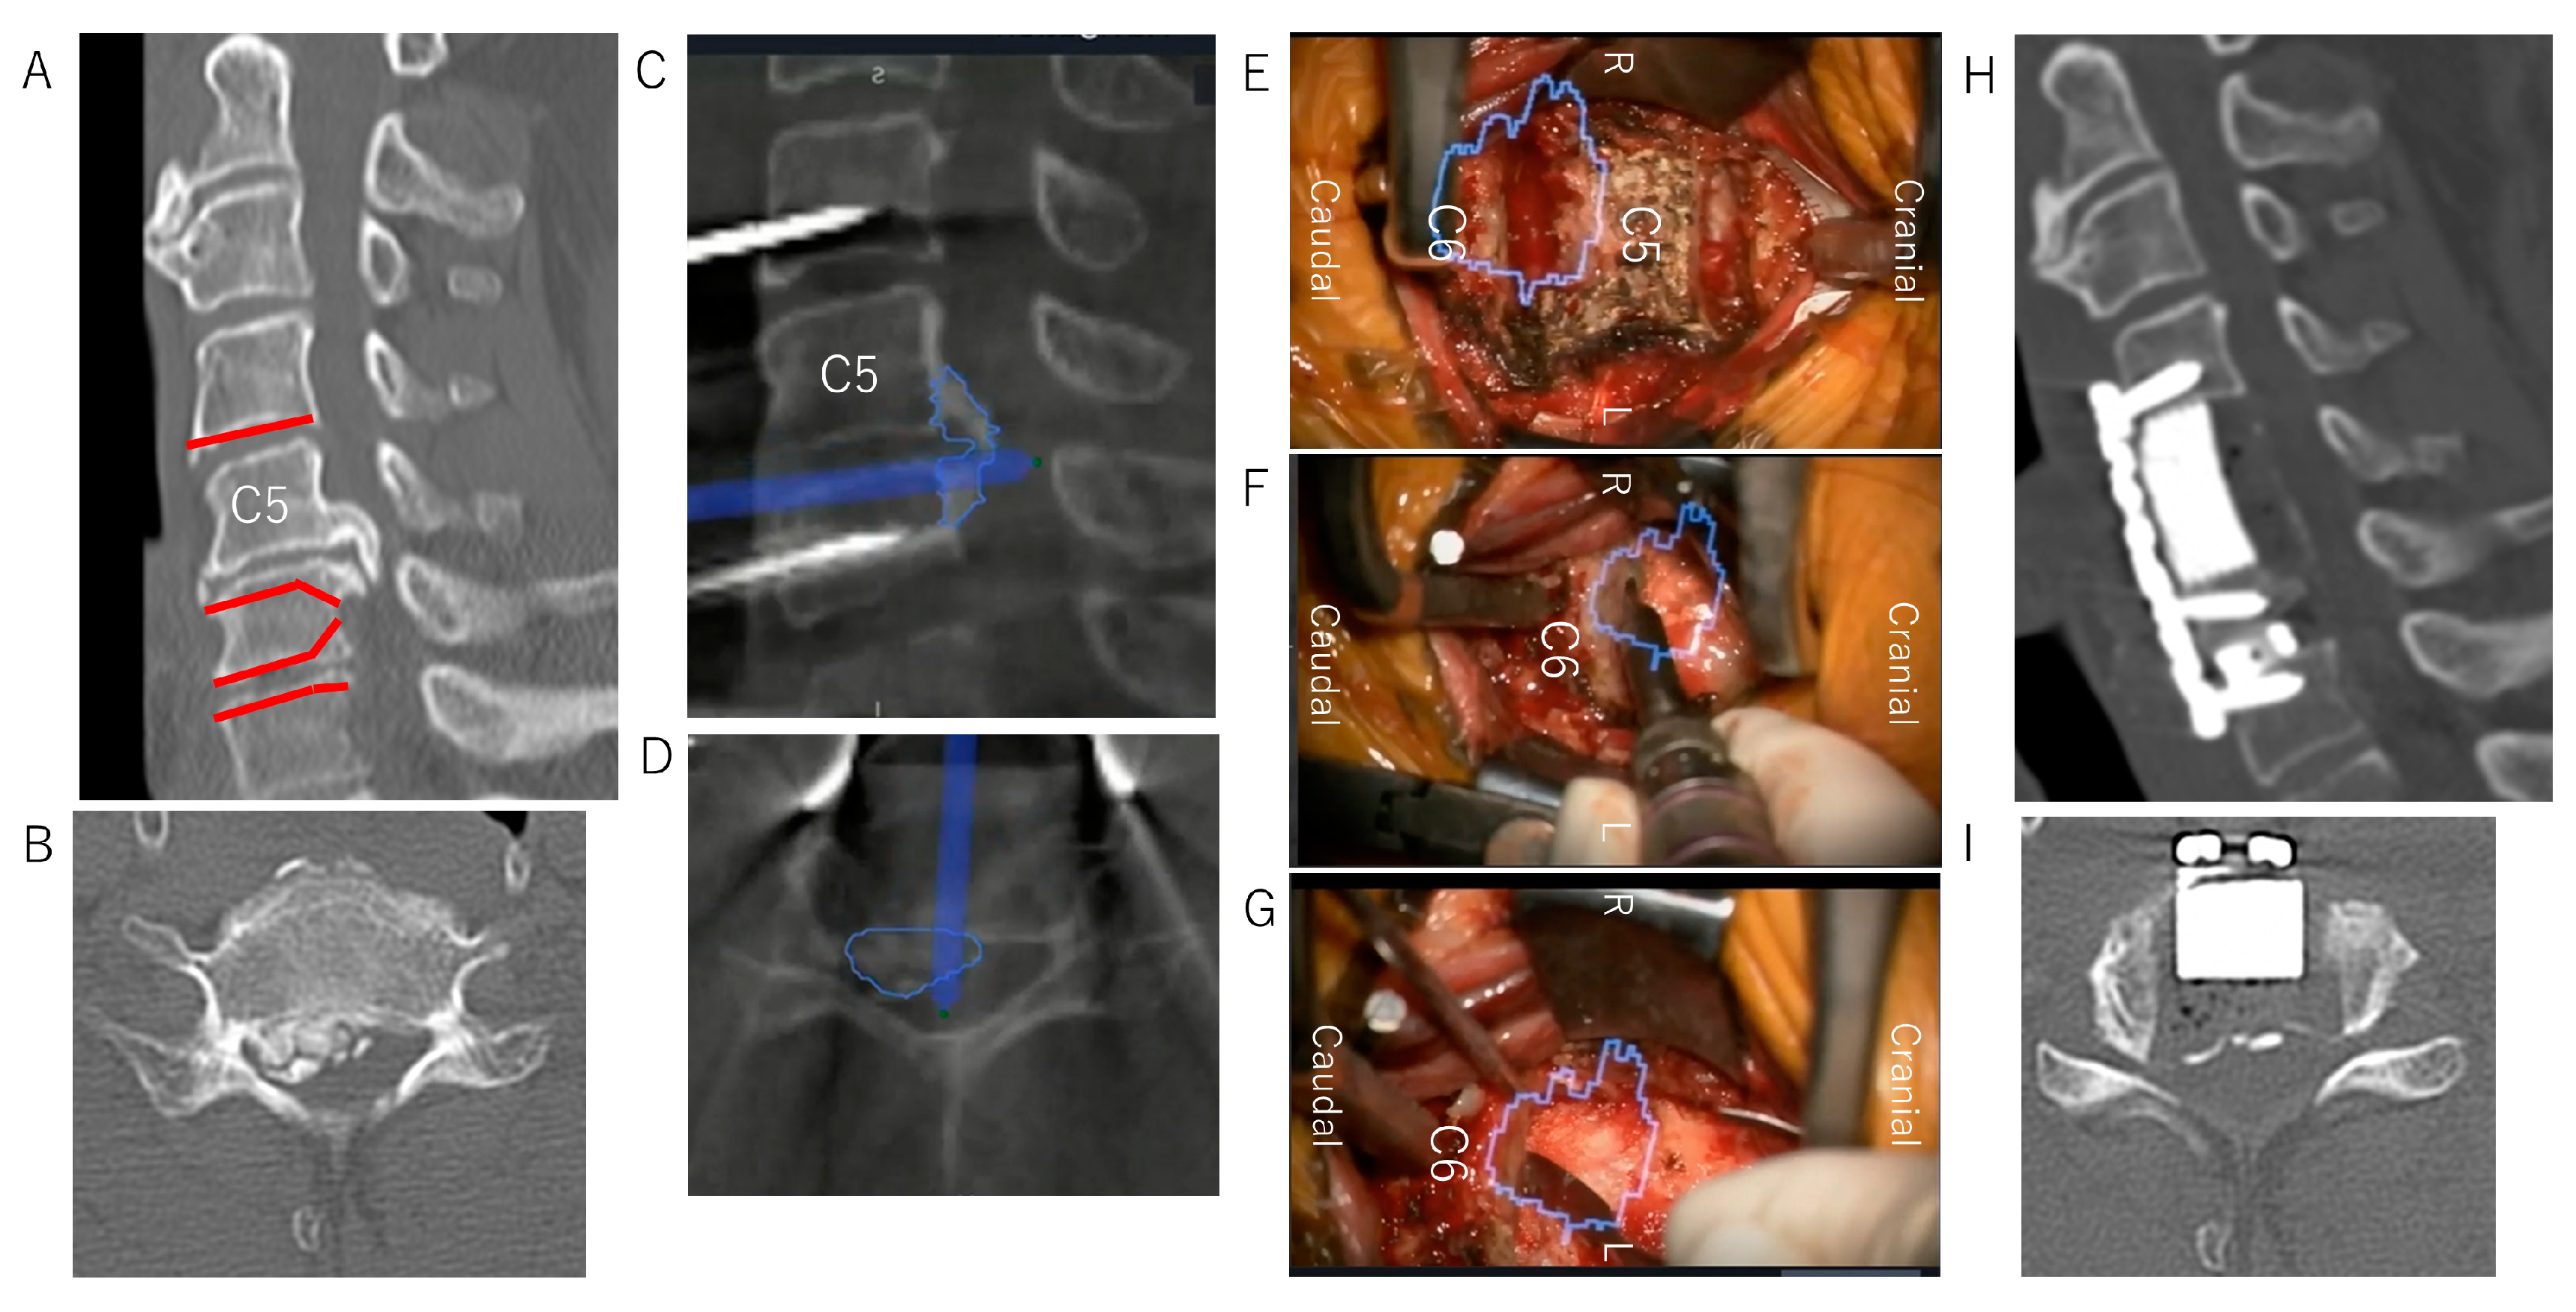

Case Presentation